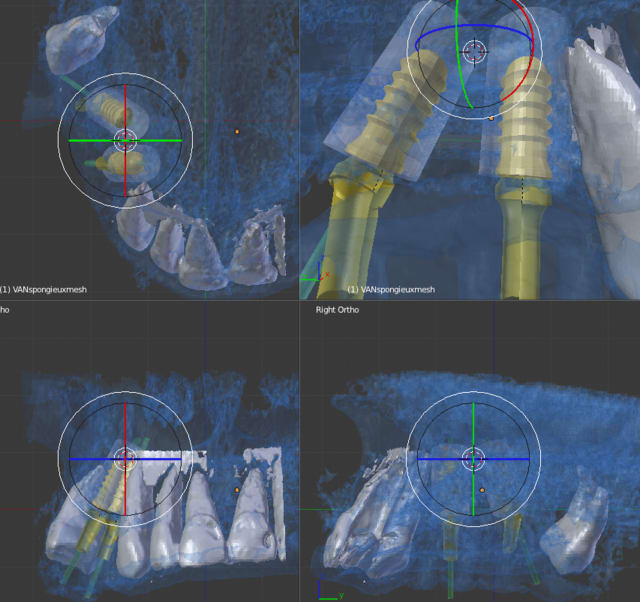

la planif. définitive du cas de la vidéo

et le premier guide à appui dentaire avec la technique de patrick

On devrait pouvoir se dispenser du guide radiologique, ce qui diminuerait les couts!!!!!!!!!!!!!!!